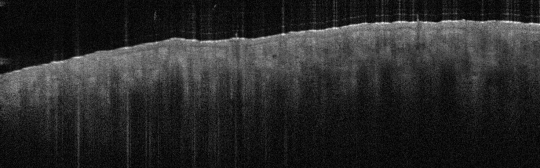

VA33: Superior Nasal Ala, Bilateral, Normal